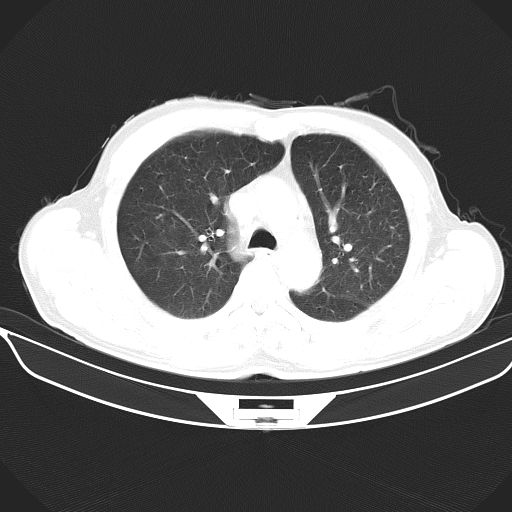

以下是引用心路寻觅在2010-3-1 10:23:00的发言:[br]1、考虑左肺上叶周围型肺癌[br]2、右上肺陈旧性病灶。[br][br][本贴已被 心路寻觅 于 2010-3-1 10:40:18 修改过]

以下是引用shuiyuan在2010-3-1 10:45:00的发言:[br]考虑左肺上叶中心型肺癌伴阻塞型炎症,邻近胸膜受侵。